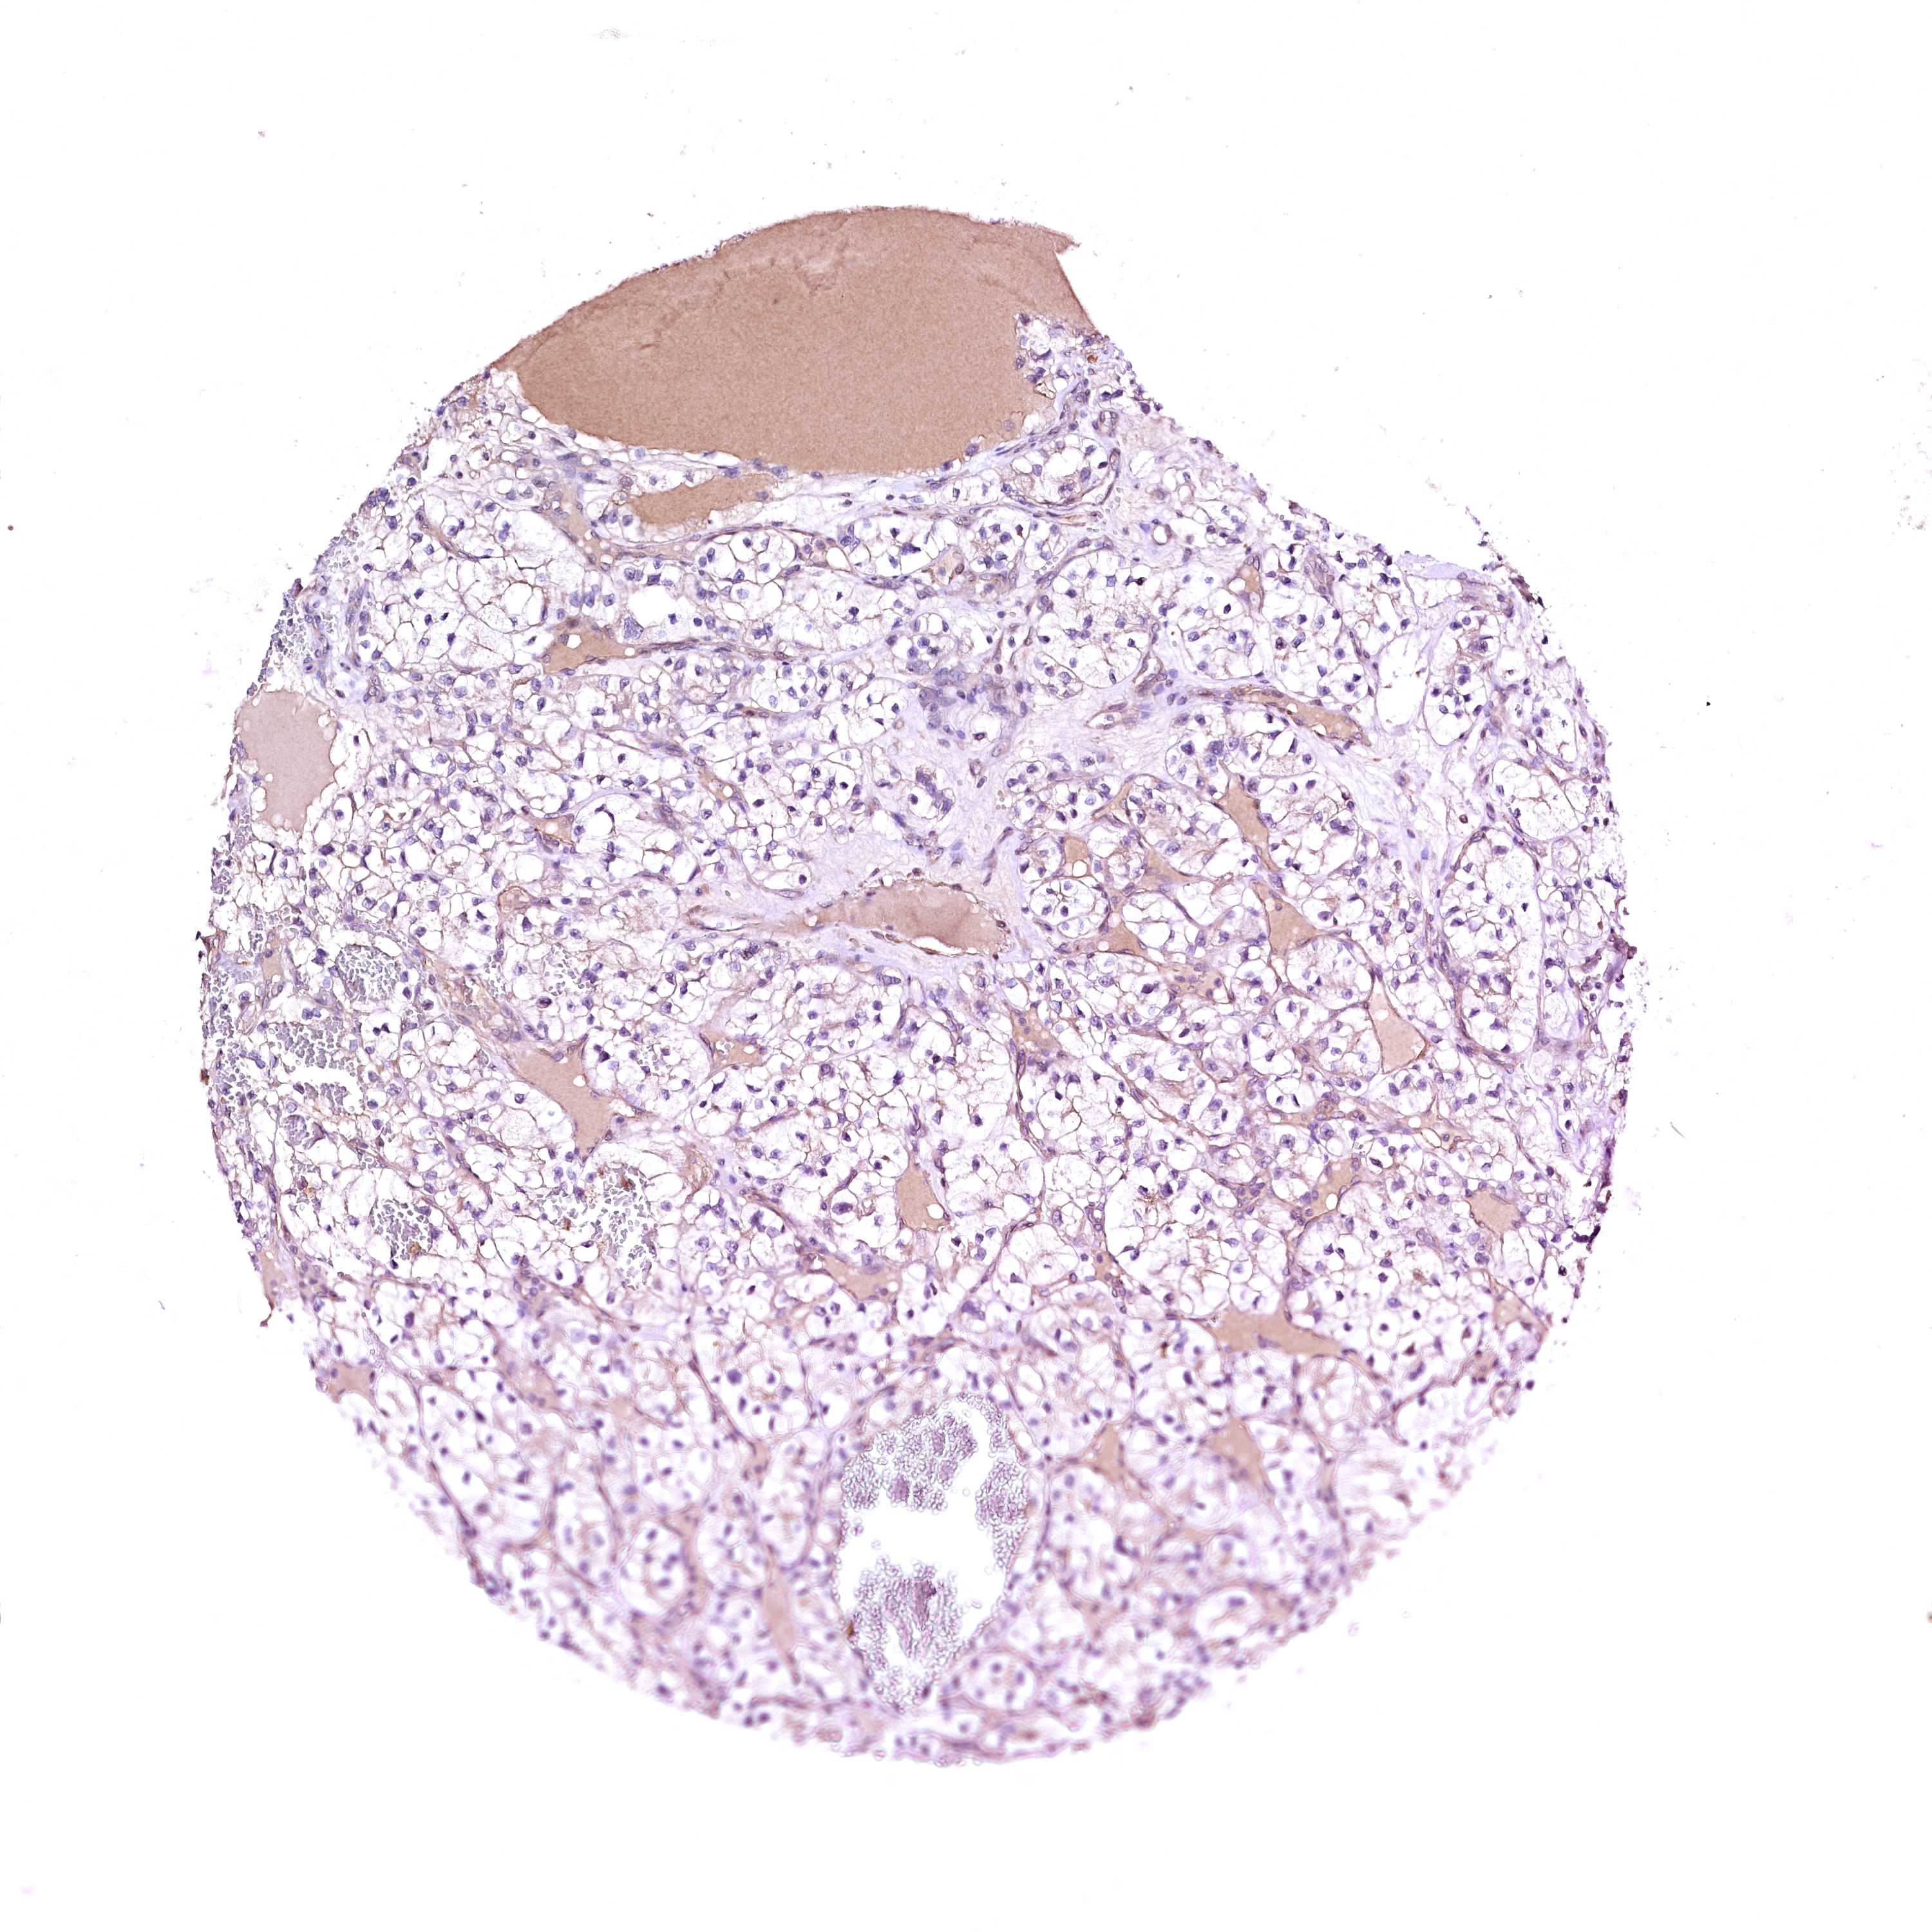

KIDNEY RENAL CLEAR CELL CARCINOMA (TCGA) - Interactive survival scatter ploti

GPR176 is not prognostic in Kidney Renal Clear Cell Carcinoma (TCGA)

: 10.65

Average pTPM 12.5

Number of samples 521